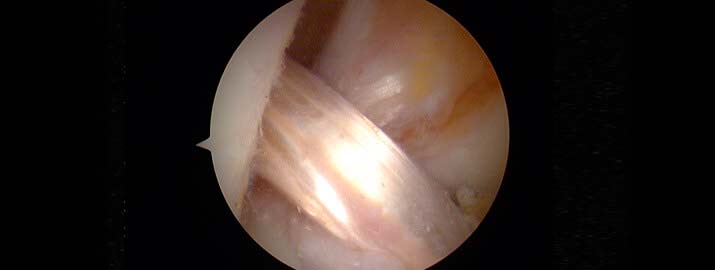

Imagen artroscópica de la reconstrucción del ligamento cruzado con isquiotibiales

Lo más aceptado en la literatura médica internacional es utilizar en estos casos otros tendones propios del paciente, los más frecuentes son el tendón rotuliano y los tendones isquiotibiales, para sustituir el LCA roto.